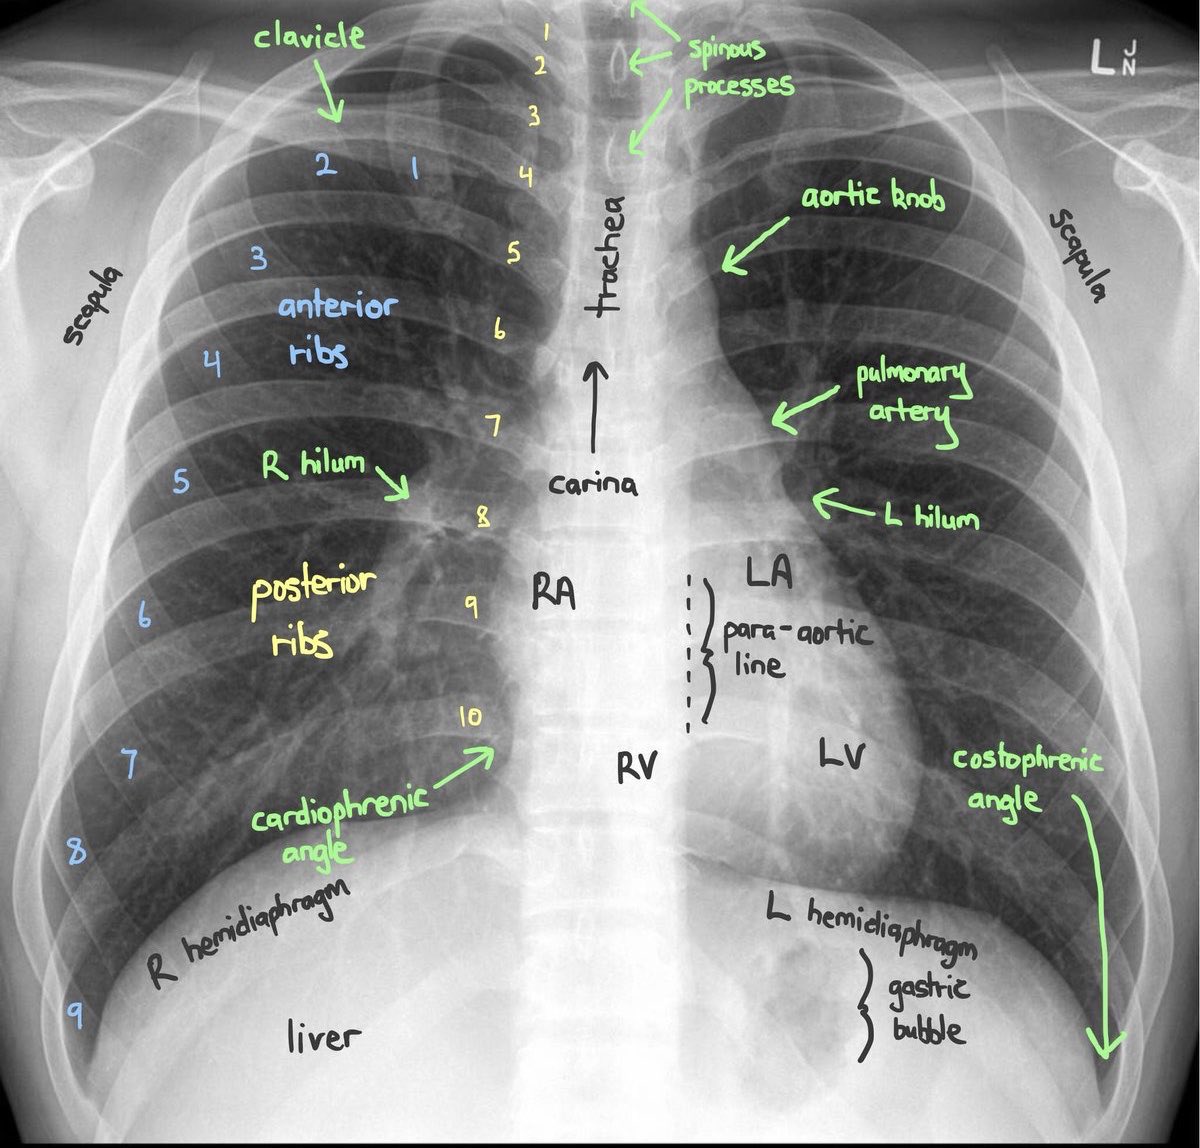

• Chest X Ray Collection

• Chest X Ray Interpretation